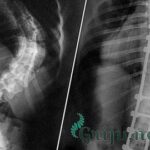

Если в ходе диагностики выявлено, что боль в области лопаток вызвана патологиями позвоночника (ущемление корешков нервов в грудном отделе, разрушение дисков, смещение позвонков) назначаются обезболивающие и противовоспалительные препараты, а также лекарства для снятия спазма в мышцах: